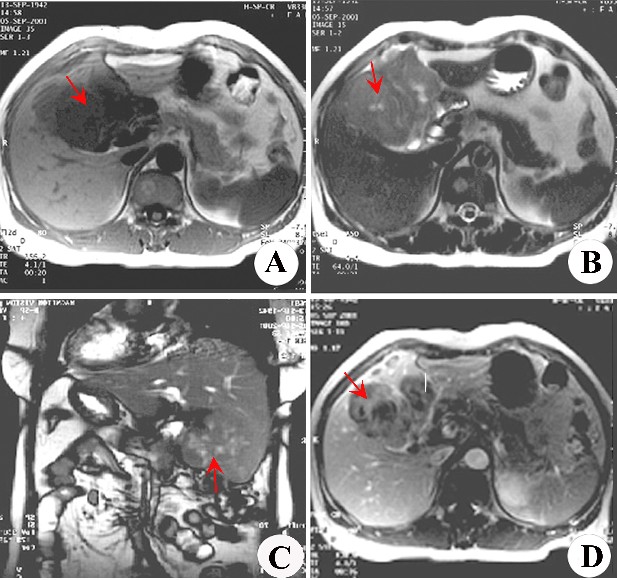

患者治疗前后影像对比图

在2014年1月,病人家属及患者辗转反侧来到了广州中医药大学金沙洲医院肿瘤综合诊疗中心,在病人不能进食的情况下,采用WB-1无创全身热疗系统结合基因治疗,治疗2疗程后,病情明显好转,能进食稀饭之类易消化食物。住院治疗一个月后,病情稳定,CT检查显示,肿瘤消失,无复发转移现象。随后病人出院,2014年5月,医院回访,病人身体状况良好,未出现不适症状。